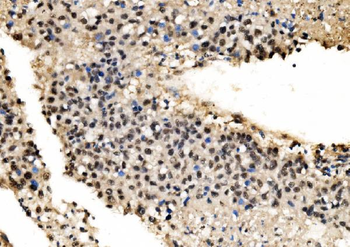

100 μl, 50 μl, 200 μl - HSC70 Mouse Monoclonal Antibody [orb704174]Featured

IF, IHC-Fr, IHC-P, WB

Human, Mouse, Rat

Mouse, Rat

Mouse

Monoclonal

Unconjugated

100 μl, 50 μl, 200 μl - ATF4 Recombinant Rabbit Monoclonal Antibody [orb704304]Featured